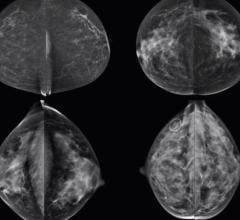

Hologic, Inc. announced that the Genius 3D Mammography exam is now the only mammogram that is FDA-approved as superior ...

Breast cancer is one of the leading causes of death of women worldwide. In Canada, according to the Canadian Cancer ...

April 26, 2017 — Nebraska Gov. Pete Ricketts signed LB195, Cheri's Law, on Wednesday, making it the 32nd state to report ...

April 14, 2017 — Kentucky and Iowa both this week joined the ranks of states with laws requiring mammography facilities ...